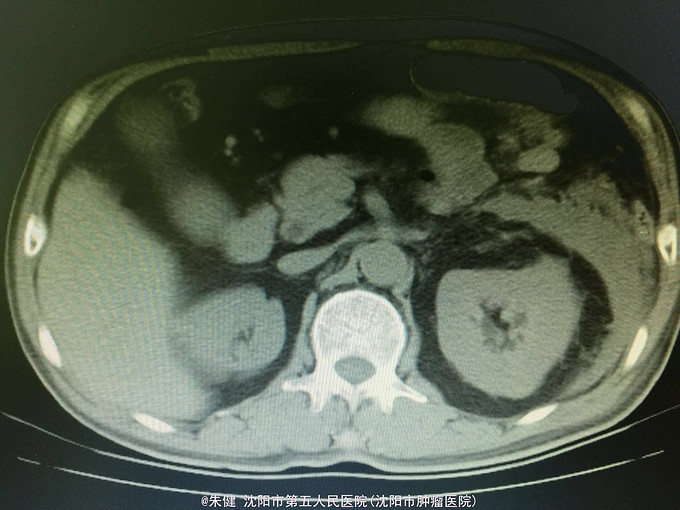

一般状态可,腹部平坦,未见肠形及蠕动波,剑突下及左侧上腹部压痛,轻度肌紧张,未及包块,无移动性浊音,肠音正常,肾区无扣痛。 辅助检查:血常规:白细胞13.6*10^9/L,中性83.3/L;尿淀粉酶:214U/L,上腹部CT:左侧胸腔积液,左肺下叶可见斑片及索条状影;胆囊增大,胆道内未及结石影;胰腺形态及密度正常,胰腺尾部周围可见索条状影及积液影。

诊断:急性胰腺炎 处理:给予禁食、补液、抗炎及抑肽酶治疗,病情逐渐好转,一周后出院。